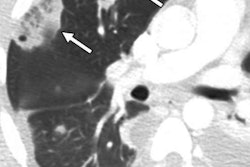

Presenter Ke Yan, PhD, from the U.S. National Institutes of Health (NIH) said he developed the multitask universal lesion analysis network (MULAN) to help radiologists save time and improve their accuracy. MULAN can help radiologists find, describe, and delineate a variety of lesions on CT, he said.

"This is the first algorithm that can do the three tasks jointly on many lesion types, thanks to the DeepLesion dataset our lab released last year," Yan told AuntMinnie.com. "It proves that computers have the capacity to remember the appearance of a lot of lesions, given sufficient training data."

After training, the algorithm yielded 84.8% detection sensitivity at a rate of one false positive per image, as well as an area under the curve of 0.96 for lesion tagging. The mean absolute error for the lesions' Response Evaluation Criteria in Solid Tumors (RECIST) diameters, calculated from the segmentation results, was 1.97 ± 2.24 mm.